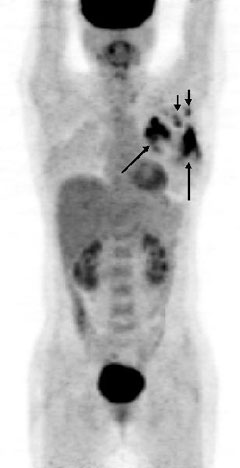

Á÷À彺Ʈ·¹½º°¡ ½ÉÇÑ ¿©¼ºÀº À¯¹æ¾Ï °Ë»ç¸¦ Á¤±âÀûÀ¸·Î ¹Þ¾Æ¾ß ÇÑ´Ù.

¿µ±¹ ·±´ø À§»ý-¿­´ëÀÇÇдëÇÐÀÇ ÇØ³ª ÄíÆÛ ¹Ú»ç°¡ Á÷Àå¿©¼º 3¸¸6õ¸í(30-50¼¼)ÀÇ 1990-2004³â ÀڷḦ ºÐ¼®ÇÑ °á°ú, Á÷Àå ½ºÆ®·¹½º°¡ °úµµÇÑ ¿©¼ºÀº À½ÁÖ, ÀÚ³à¼ö, üÁß, ¿¬·É°ú °ü°è ¾øÀÌ À¯¹æ¾Ï ¹ß»ý·üÀÌ 30% ³ô°Ô ³ªÅ¸³µ´Ù.